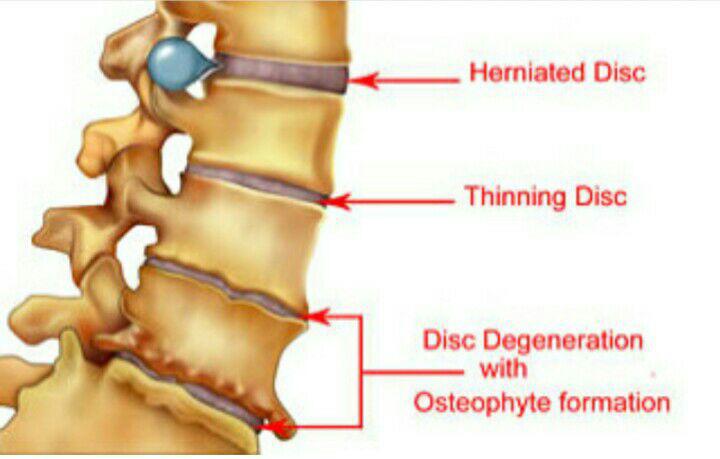

-درمان کمردردهای مزمن

-لیزر(جراحی بسته) دیسک کمری

-درمان آرتروز مفاصل

-درمان دردهای مزمن , ستون فقرات , سردردهای مزمن

-PRP و اوزون تراپی آرتروز مفصلی

-اوزون تراپی دیسک بین مهره ای

-درمان تنگی کانال نخاعی غیرقابل جراحی

دردهای اسکلتی عضلانی (کمردرد، گردندرد، زانودرد، آرتروز)